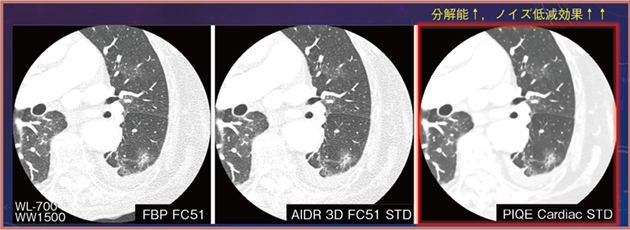

4.Precise IQ Engine(PIQE)

今後,期待される技術に,キヤノンメディカルシステムズの「Precise IQ Engine(PIQE)」がある。Aquilion ONEに搭載されているPIQEは,ディープラーニングを応用した超解像画像再構成技術で,Aquilion Precisionのデータを教師とし,MBIR(Model Based Iterative Reconstruction)やDLRを教師データに適用しているため,空間分解能が高く,かつ優れたノイズ低減効果を有し,粒状性を維持することができる(図3)。現状,実装されているのは心臓の再構成関数(PIQE Cardiac)のみであるが,縦隔条件の画像にPIQE Cardiacを適用したところ,左房壁や心筋などにほぼノイズを認めず,視覚的,定量的な評価における有用性が期待される。

図3 PIQEによる画質改善効果